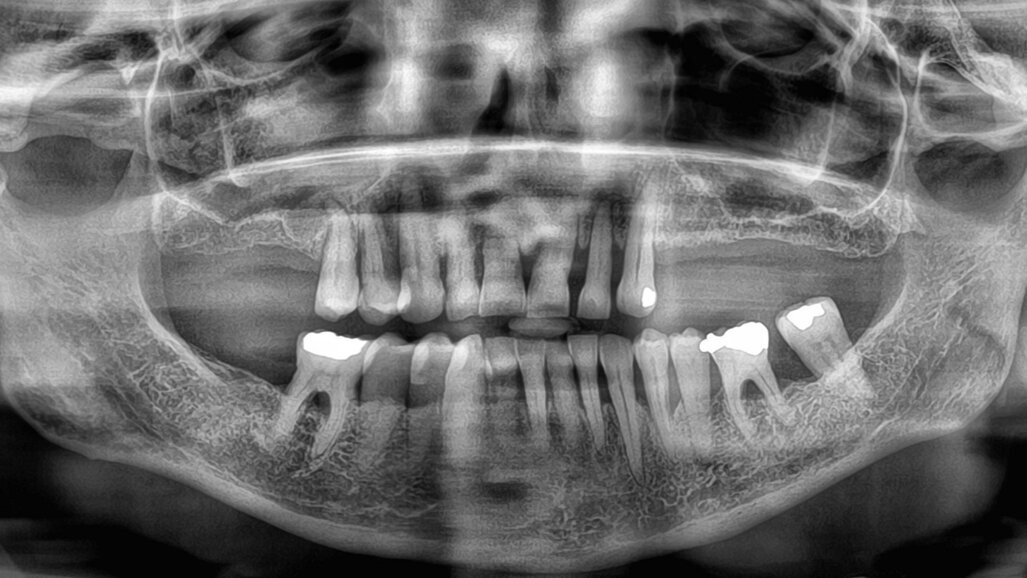

Fig. 1: Pre-op radiograph. (All images: Marco Degidi, Gianluca Sighinolfi)

Owing to chronic periodontal disease, the 65-year-old female patient had lost premolars and molars in the maxillary arch (Fig. 1). It was decided to perform her treatment with dental implants.